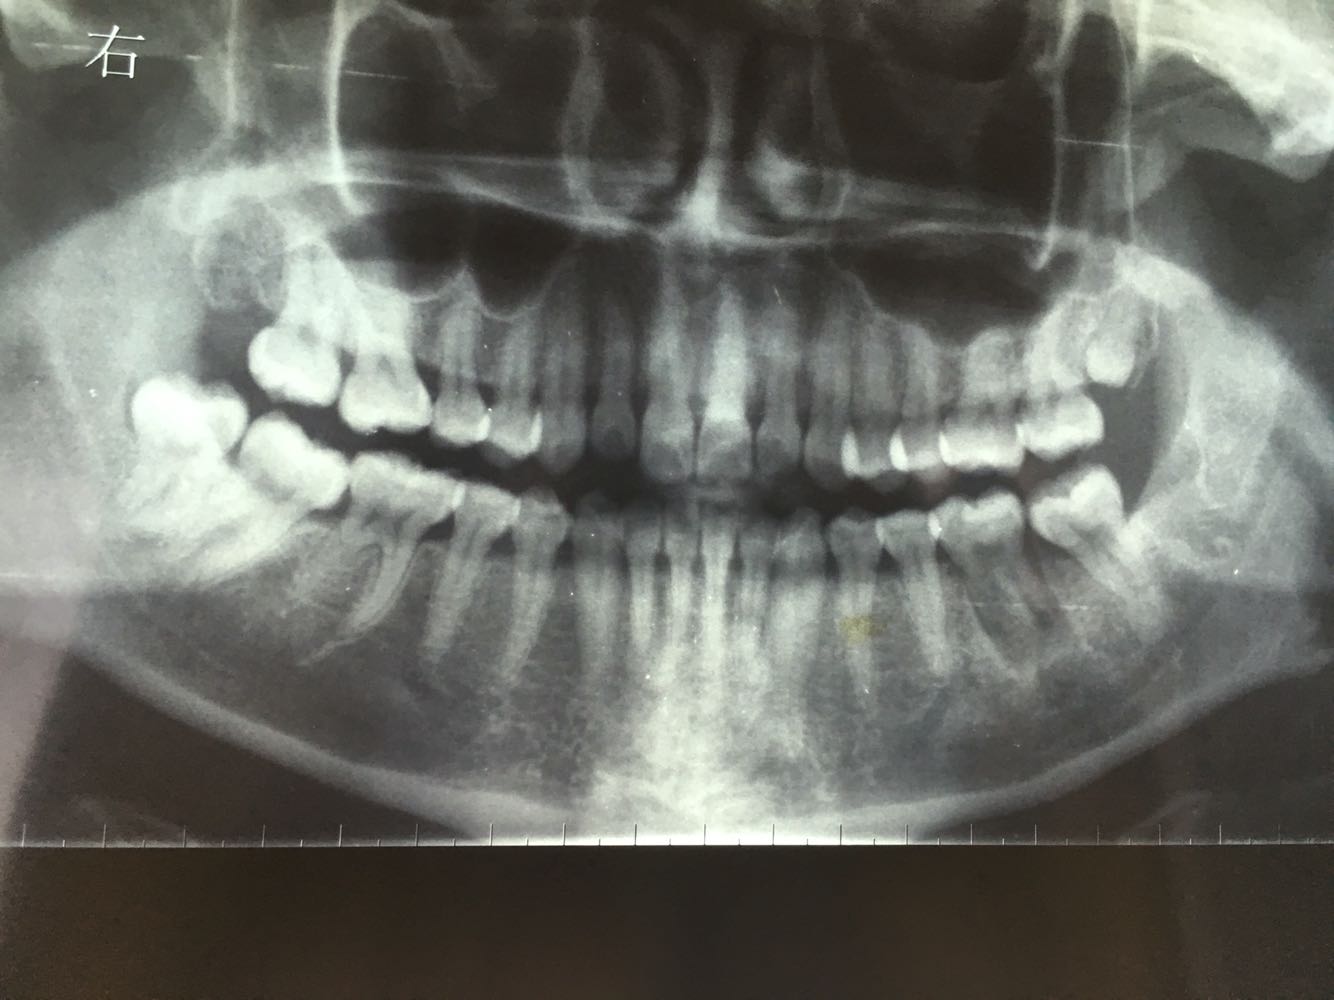

主诉:左下后牙反复肿痛

左下6残根,8正位,对颌未萌出,

讨论:患者本来是要求拔除左下6残根的,进修医生拔除残根后本人建议自体牙移植,患者接受了我的经验,把8拔除后移植到6的位置,目前还在随访中